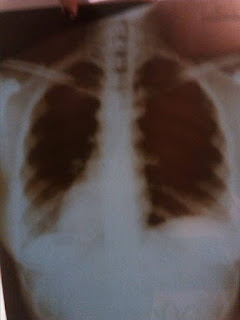

![]() |

| These are my pneumonia free lungs (after 2 months of it!)! :D |